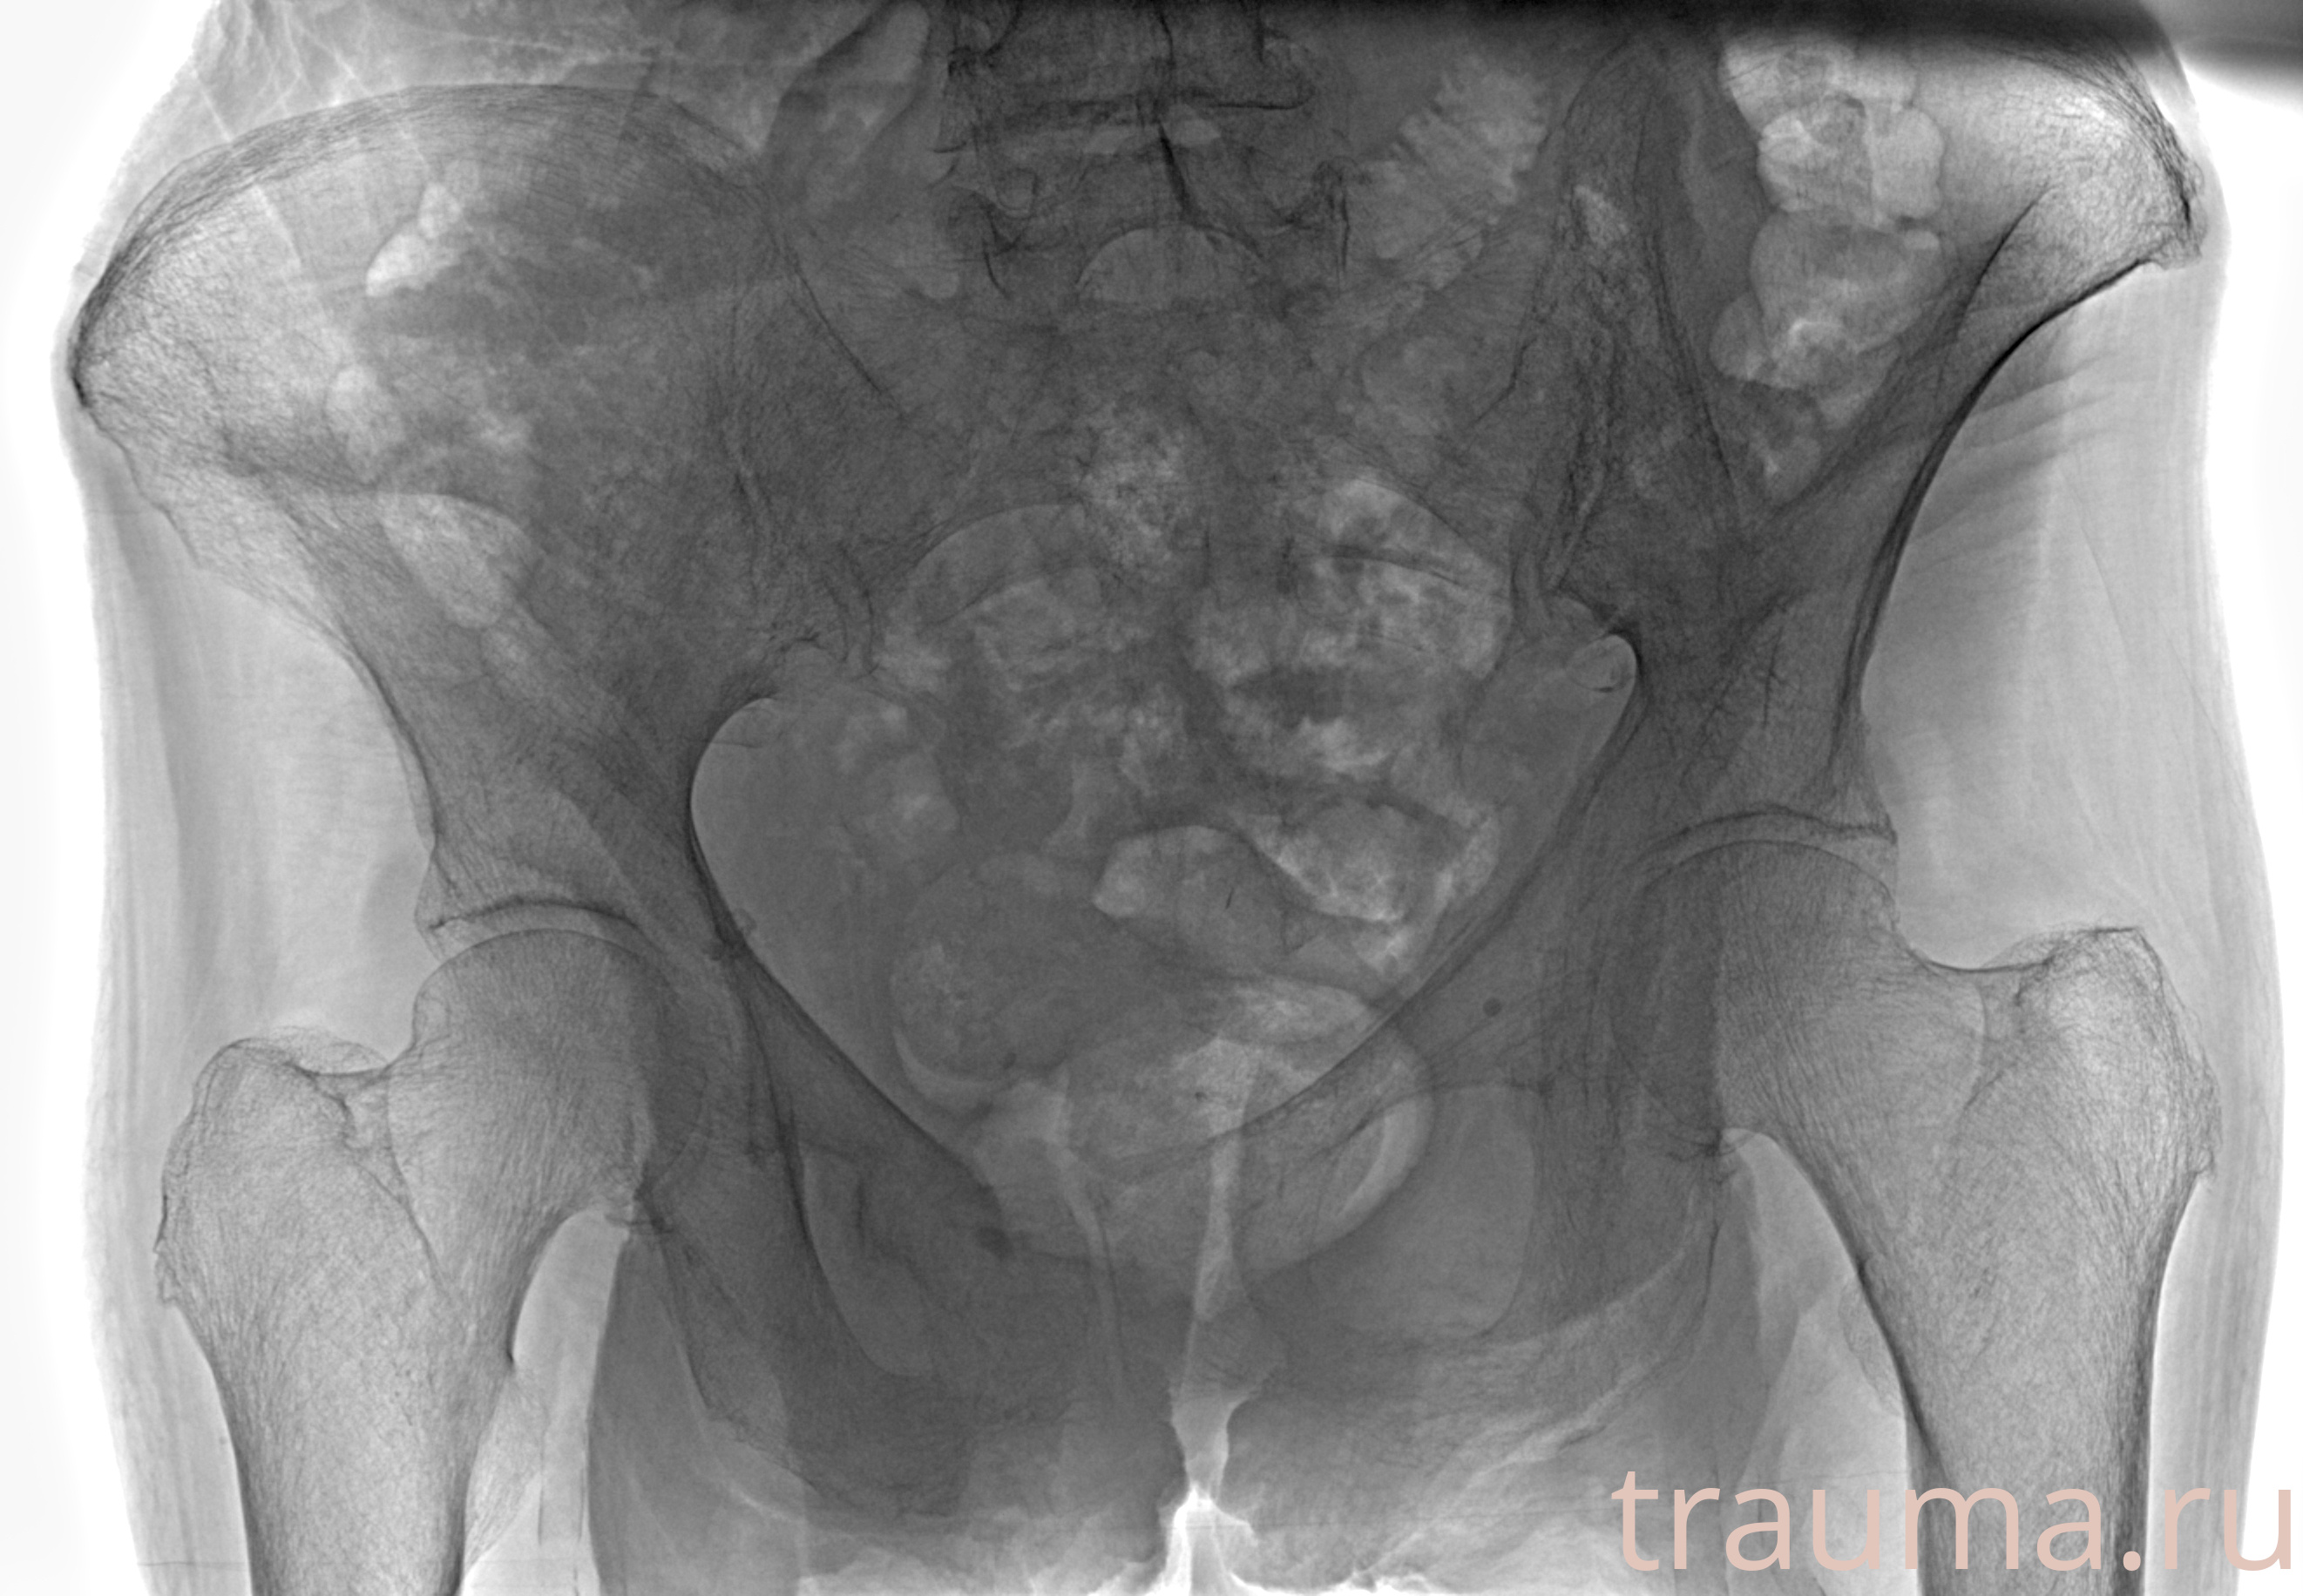

Рентгенограммы

Рентген на дому: по вашему адресу приезжает врач-рентгенолог, травматолог-ортопед с мобильным рентгеновским аппаратом, проводит диагностику травмы или заболевания, делает необходимые рентгенограммы, дает рекомендации по дальнейшему лечению. Получить качественные снимки в домашних условиях возможно благодаря уникальной методике, разработанной МосРентген Центром для института  Склифосовского